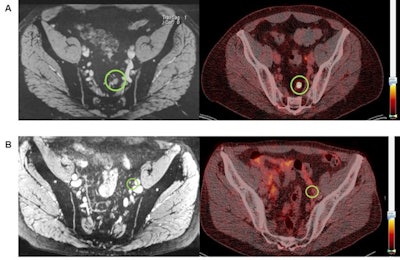

One set of images (A) shows a 7-mm diameter lymph node that is positive on both nano-MRI and PSMA-PET/CT in a patient's left pararectal region. For comparison, the other set of images (B) shows a 4-mm diameter lymph node diagnosed as positive on nano-MRI (left) but negative on PSMA-PET/CT (right) with no Ga-68 PSMA tracer uptake in the region (green circle). Images courtesy of the Journal of Nuclear Medicine.Nano-MRI was significantly superior by detecting 160 suspicious lymph nodes (89%) in all 33 patients (100%), compared with 71 suspicious lymph nodes (40%) discovered by PSMA PET/CT in 27 patients (82%) (p < 0.001). Of all 160 suspicious lymph nodes, nano-MRI exclusively discovered 108 of them (60%), while PSMA PET/CT was the sole identifier of 19 (11%) suspicious lymph nodes and both modalities similarly spotted 52 (29%) suspicious abnormalities.